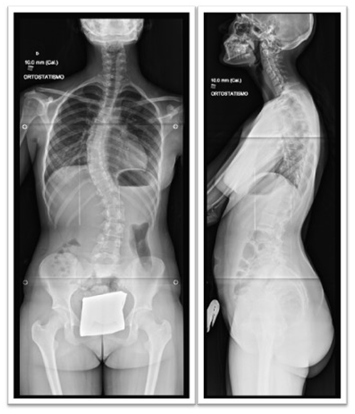

A 15-year-old girl was referred to our orthopaedic department due to spine deformity and lumbar pain. Physical examination showed a right rib hump and shoulder asymmetry. The radiographic study showed a curve type 6BN of Lenke, with a left lumbar curve centred in L2 and a Cobb angle of 43º and a right thoracic curve centred in T8 and a Cobb angle of 25º. The patient was proposed for surgery, undergoing a posterior correction and fusion surgery with a pedicle screw selective construct between D5 and L4. During the procedure there was no evidence of pedicle screw misplacement.

Pulmonary complications after AIS correction surgery are rare. A study with 702 AIS patients reported only 10 respiratory complications. These complications do not seem to be related to factors like Lenke curve type, region of the major curve or even the number of instrumented levels. Among those complications, hemothorax is a quite rare one. The most commonly described causes of hemothorax after posterior correction and fusion surgery are thoracoplasty and misplaced pedicle screws.1,5 Pedicle screw fixation is considered as gold standard procedure in which concerns the spinal deformity correction2,6 (Figure 1).